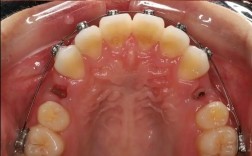

矫治器粘戴/佩戴

- 固定矫治器:在目标后牙粘接托槽,弯制个性化弓丝(如镍钛圆丝、不锈钢方丝),通过结扎丝或橡皮圈固定;